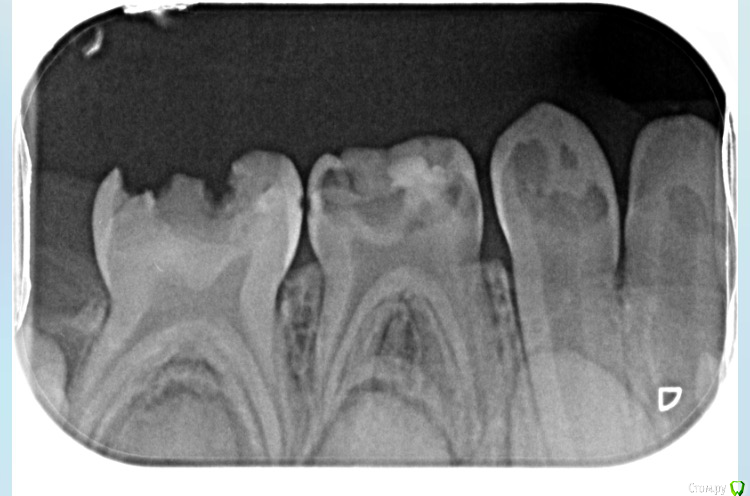

DAV86.06 Опубликовано 2 октября, 2017 Поделиться Опубликовано 2 октября, 2017 (изменено) Добрый вечер! Подскажите пожалуйста. Ребёнку 4года на жевательные зубки нижние предлагаютпоставить коронки. На сколько это актуально в нашем случае или можно обойтись пломбой? Изменено 2 октября, 2017 пользователем DAV86.06 1 Ссылка на комментарий

DAV86.06 Опубликовано 2 октября, 2017 Автор Поделиться Опубликовано 2 октября, 2017 Передние верхние зубы предлагают удалить тк лечить их смысла нет. И ещё нам насчитали 8 пульпитов♀ Ссылка на комментарий

ЕленаВалерьевна Опубликовано 2 октября, 2017 Поделиться Опубликовано 2 октября, 2017 с короночками будет надежнее, про пульпиты согласна с вашим доктором. по поводу передних зубов точно не могу сказать, только по снимку сложно ориентироваться, возможно и полечить получится. 1 Ссылка на комментарий